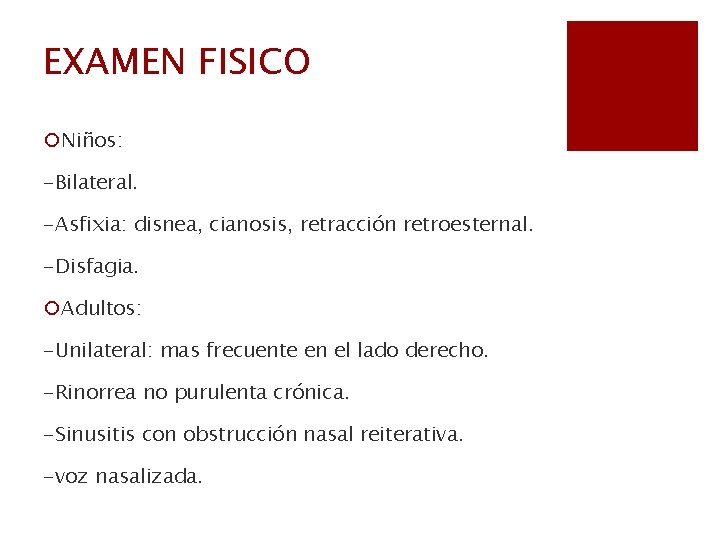

EXAMEN FISICO ¡Niños: -Bilateral. -Asfixia: disnea, cianosis, retracción retroesternal. -Disfagia. ¡Adultos: -Unilateral: mas frecuente en el lado derecho. -Rinorrea no purulenta crónica. -Sinusitis con obstrucción nasal reiterativa. -voz nasalizada.